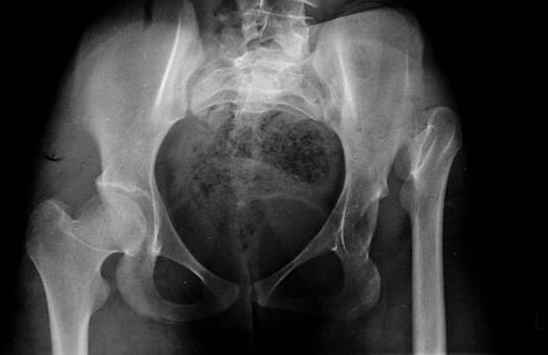

Moghno i tak kak sdelali my: pelvic support + tibial and equinus correction .

Слайд 1

Слайд 2

Слайд 3

Слайд 4

Devushka predstavlennaya na snimke nachala s LLD 9 cm, valgus deformation of the tibia, huge Trendelenburg( vidno na snimke).

Seichas : no LLD ,no Trendelenburg, reasonable hip motion.A samoe glavnoe ei ne predstoit kaghdye 10-15 let delat revision THR.